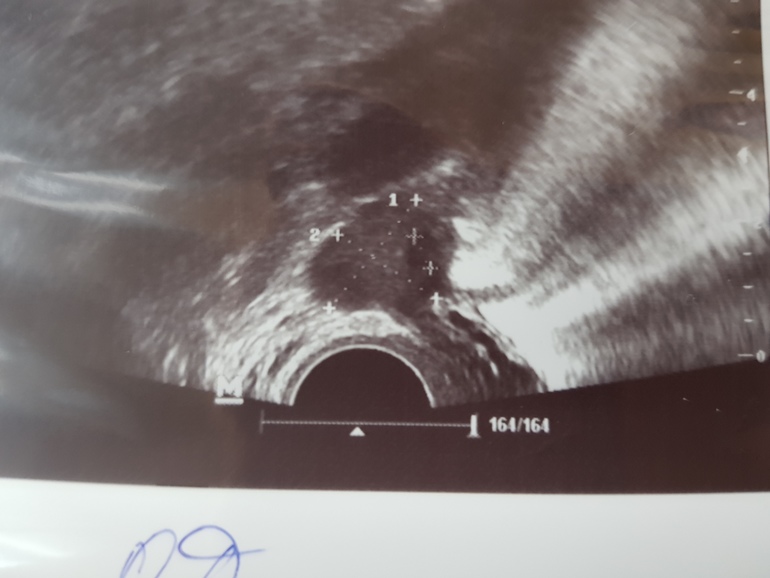

И фоточки для себя, правый я: